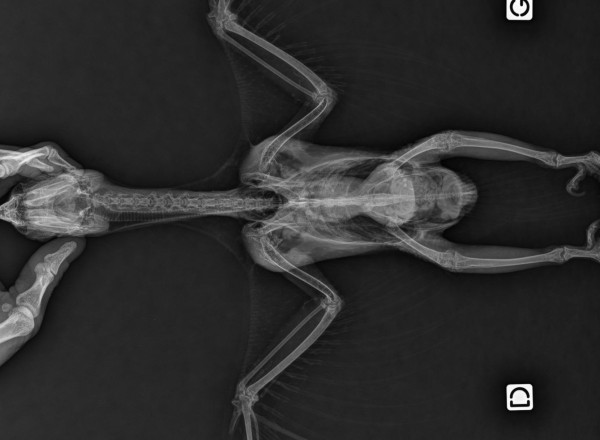

La radiographie vétérinaire repose sur l’utilisation des rayons X pour obtenir une image du corps et des différents organes de votre animal, qu’il s’agisse d’un chien, d’un chat ou d’un nouvel animal de compagnie (NAC). Il s’agit d’un examen en médecine vétérinaire qui constitue un outil essentiel au diagnostic de santé et à la prise en charge de votre animal de compagnie.

En radiographie, les tissus apparaissent en nuance de gris, du noir au blanc : on peut y voir les graisses, les tissus mous, les structures minéralisées (dont les os), et le métal.

-En orthopédie : en cas de membre douloureux ou de boiterie

-Les membres douloureux : en cas d'inconfort ou de boiterie

Il est enfin incontournable lors de la prise en charge initiale des animaux traumatisés, après une chute ou un accident (recherche de fractures, d’épanchement, de lésions thoraciques).